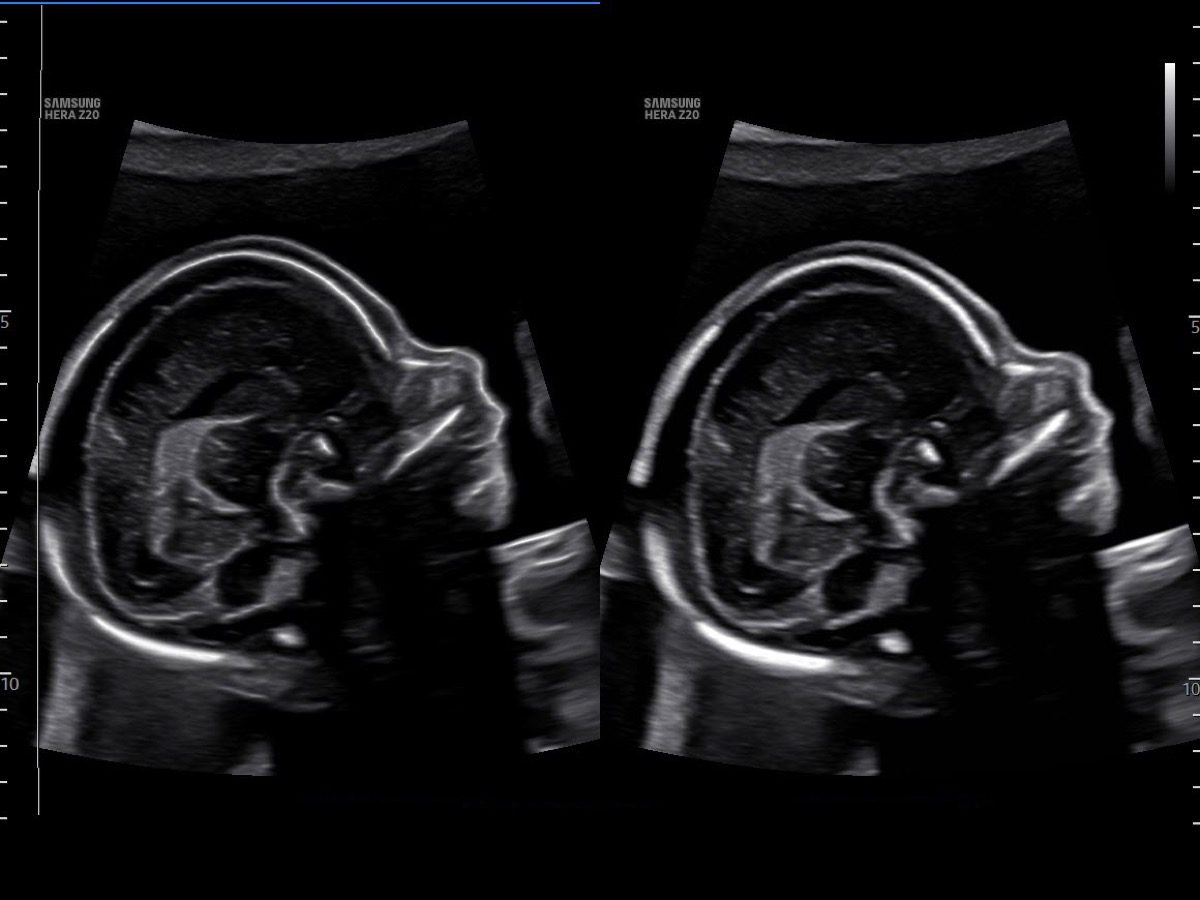

Comprehensive, advanced and expert MFM care for high-risk pregnancies

- Fetal anomalies